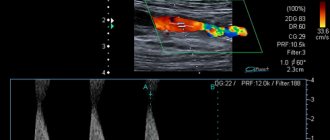

Врачи педиатрического отделения Клинического госпиталя на Яузе располагают всеми возможностями для тщательной и всесторонней диагностики сердечно-сосудистых заболеваний у детей. В частности, собственная лаборатория делает необходимые анализы, есть возможность сделать УЗИ сердечно-сосудистой системы, ЭКГ, регулярно контролировать уровень сахара и холестерина в крови.